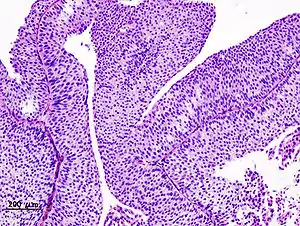

Histopathology of urothelial carcinoma of the urinary bladder. Transurethral biopsy. H&E stain